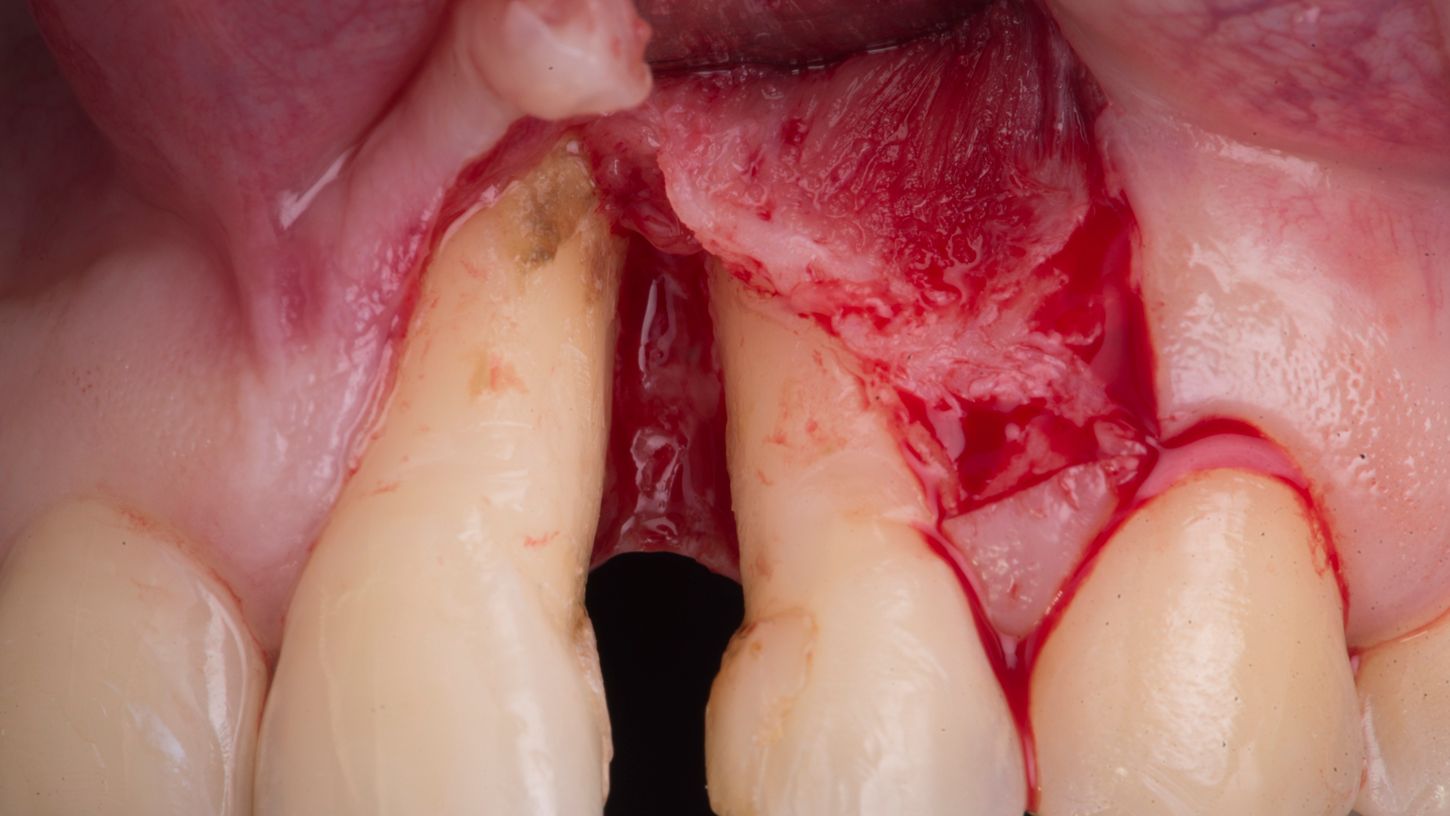

A CTG wall technique was conducted with a release incision at the distal aspect of the lateral incisor (Fig. 3).

Fig. 3

Meticulous scaling and root planing was performed (Fig. 4) and revealed a combined 1- and 2-wall osseous defect (Fig. 5).